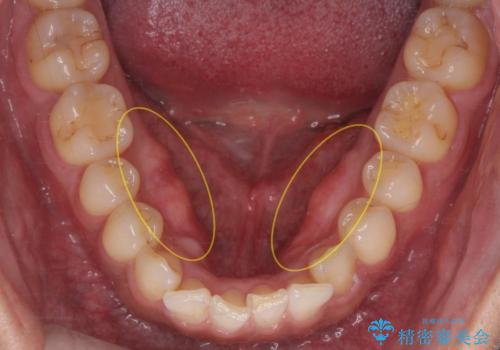

滑舌が気になる 舌小帯の切除

- 舌を動かしにくいとのことで来院されました。

舌の裏側にある舌小帯という部分が短い状態だったため、舌小帯の切除をすることとなりました。

術後の治りも良く、以前よりも話しやすくなったと大変喜んでいただけました。